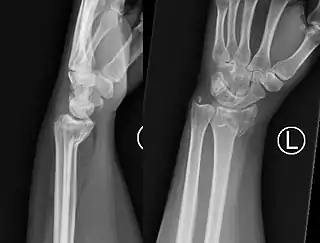

Fractura de Goyrand-Smith

La fractura de Goyrand-Smith o fractura de Smith (o fractura de Colles invertida) es una fractura del extremo distal del radio con desplazamiento palmar del fragmento y la mano, respecto del radio; esto produce la deformidad en pala de jardinería. Su epónimo se debe al médico, cirujano y político francés Gaspard Goyrand[1] y al cirujano ortopédico irlandés Robert William Smith que la describe en su obra Treatise on Fractures in the Vicinity of Joints, and on certain forms of Accidents and Congenital Dislocations, publicada en 1847.[2]

El fragmento de fractura distal se desplaza de forma volar (ventralmente), a diferencia de la fractura de Colles, que el fragmento se desplaza dorsalmente. Dependiendo de la gravedad del impacto, puede haber uno o varios fragmentos y puede o no afectar la superficie articular de la articulación de la muñeca.

El diagnóstico inicial es clínico mediante al exploración, haciendonos sospechar la presencia de este tipo de fractura si se presentan los signos detallados arriba. Ante esta sospecha, el diagnóstico final apropiado de este tipo de fracturas necesita la realización de una radiografía simple del antebrazo distal y del carpo en al menos dos proyecciones: antero-posterior y lateral. En algunos casos, una vez realizada la radiografía simple, cuando las imágenes muestren que se trata de una fractura multifragmentario o compleja, la realización de una tomografía computarizada simple de la lesión puede ser útil para guiar el tratamiento.